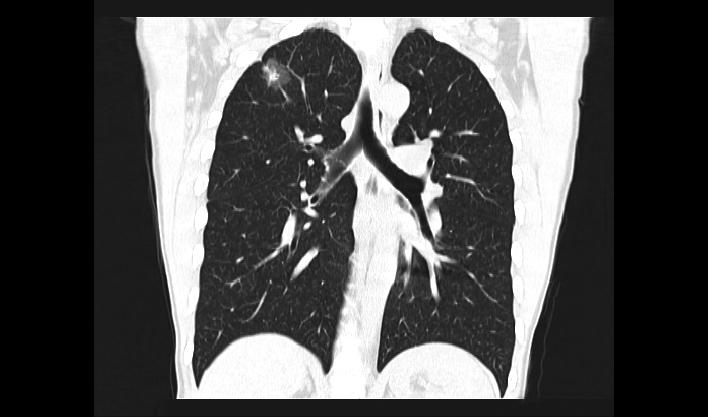

La matriz de reconstrucción de 1024*1024 amplía los datos de la imagen cuatro veces. Combinado con imágenes de corte fina, incluso las lesiones más invisibles son claramente visibles.

Captura instantánea para evitar artefactos por movimiento respiratorio, lo que mejora la tasa de éxito de los exámenes.